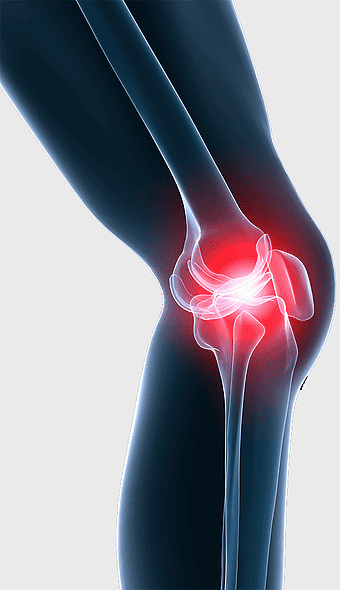

stem-cell therapy for knee pain, patellofemoral pain syndrome treatment, knee joint injection therapy, platelet-rich plasma for knee, human leg joint pain relief, medical imaging of knee joint, orthopedic knee treatment options -